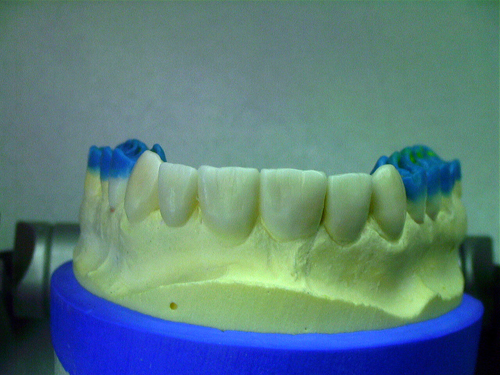

ABSTRACT El Bruxismo es una entidad patológica en la que concurren diferentes factores. Entre ellos el stress que conlleva consigo la vida moderna, constituye el Factor Predisponente sobre el que se ha abundado en innumerables tratamientos de tipo general, actuando sobre la psiquis y el comportamiento del individuo, ya sea con fármacos o bien mediante medios psicológicos. Sin embargo, como tantos desequilibrios provocados por el stress, confluyen siempre con un Factor Desencadenante, que en el caso del Bruxismo se encuentra en las desarmonías entre los componentes varios del Sistema Estomatognático. DESARROLLO Paciente varón, de 43 años, constitución atlética. A la inspección se observan desgastes oclusales que alcanzan la calidad de Facetas Parafuncionales, con dentina expuesta y empastes totalmente gastados y evidentes signos de falta de Disclusión Canina de ambos lados. Sobre dicho montaje se realiza un Encerado Progresivo de Diagnóstico, aportando en el mismo los elementos necesarios para obtener todos los principios básicos de una Oclusión Orgánica. FIG. 6 a 24 Una vez aprobado el fisiologismo de la oclusión en el articulador, se reproducen modelos de yeso con la nueva situación, y se estampa un SET UP en cada maxilar. FIG. 25/26 Procedemos entonces al tallado de las piezas correspondientes a la Guía Anterior, y rebasamos los estampados, creando en boca una nueva situación desoclusiva, que permanece en boca durante los pocos días que transcurren entre la primera y segunda visita de trabajo. FIG. 27/33 Ya abordando en esta segunda visita los sectores posteriores, tanto superiores como inferiores, tallamos siempre de manera supragingival, destacando la importancia vital de la forma obtenida en las provisionales, a las que abrimos plenamente las troneras para lograr una correcta higiene. FIG.34 a 43 FIG. 44 a 52 Efectuados los colados en oro y probados en boca, en el laboratorio se confecciona el bizcochado de la nueva Guía Anterior, la que puede o no copiarse de la Guía Anterior provisional, mediante la técnica denominada Trayectoria Funcionalmente Generada, que consiste en realizar en la platina del articulador un registro estereográfico sobre acrílico Duralay en polimerización. FIG. 57/58 Ajustados todos los detalles mediante esta técnica, se instala en boca en forma Provisional y se deja funcionando una semana o dos, al cabo de las cuales se chequean las disclusiones , los ajustes, la eficacia masticatoria, la carencia de sintomatología articular y muscular. FIG.59 a 63 PIE DE FOTO FIG.9 OBTENCIÓN DE LA GUÍA ANTERIOR FIG.10 Y 11 PITOMBOS. ALINEAC. TRIDIMENSIONAL FIG.12 PITOMBOS. DISCLUSIÓN DER. FIG.13 PITOMBOS. DISCLUSIÓN IZQ. FIG.14 WILSON INF. FIG.15 WILSON SUP. FIG.16 BOCA DE PEZ INF. FIG.17 BOCA DE PEZ SUP. FIG.18 VISTA OCLUSAL FIG.19 O.R.C. FIG.20 DISCLUSIÓN DERECHA FIG.21 CRESTAS TRIANG. INT. FIG.22 CRESTAS TRIANG. INT. FIG.23 CRESTAS TRIANG. INT. FIG 24 CRESTAS TRIANG. INT. FIG.59 DISCLUSIÓN IZQ. FIG.60 DISCLUSION IZQ. FIG.61 DISCLUSIÓN DER. FIG.62 DISCLUSION DER. FIG. 63 AJUSTE PERIFÉRICO